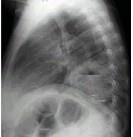

问题 女,36岁,发热,胸痛咳脓痰十余天,胸部正侧位如图,最可能的诊断为 ( )

选项 A.左下肺周围型肺癌并空洞形成 B.左下肺脓肿 C.左下肺空洞型肺结核 D.左侧包裹性液气胸 E.急性胃扩张

答案 B